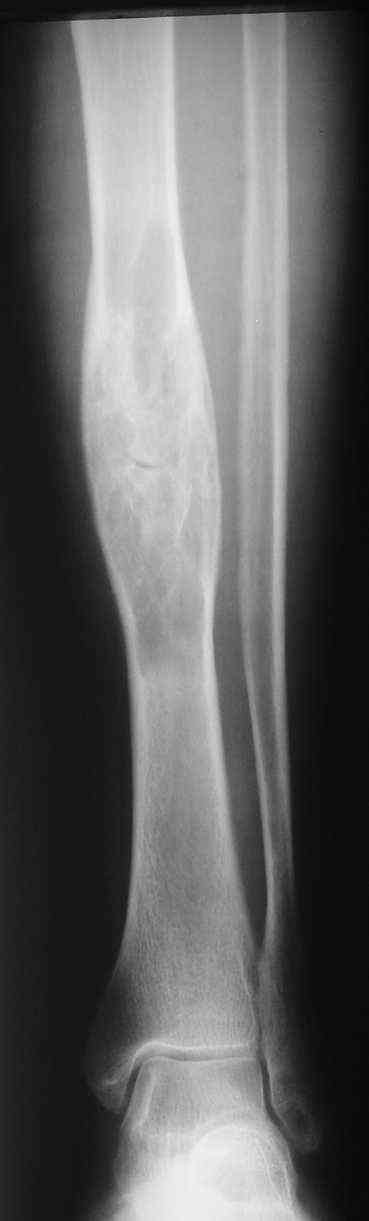

Здравствуйте, уважаемые коллеги. Женщина 62 лет с гигантоклеточной? опухолью диафиза большеберцовой кости.

В анамнезе хроническая травматизация. Заметила месяца три назад, не болит. Кожа над образованием не изменена. Рентгенограммы прилагаются. Наша военно-научная мысль бьется в направлении резекции кости в пределах здоровых тканей,фиксации блокированным стержнем с последующим выращиванием костного регенерата. Или лучше выполнить краеву резекцию, эксколхеацию и пластику дефекта (предварительно верифицировав диагноз при помощи трепан-биопсии)? Есть некоторые сомнения, что это действительно ОБК. Хотелось бы ваше мнение. Алексей.